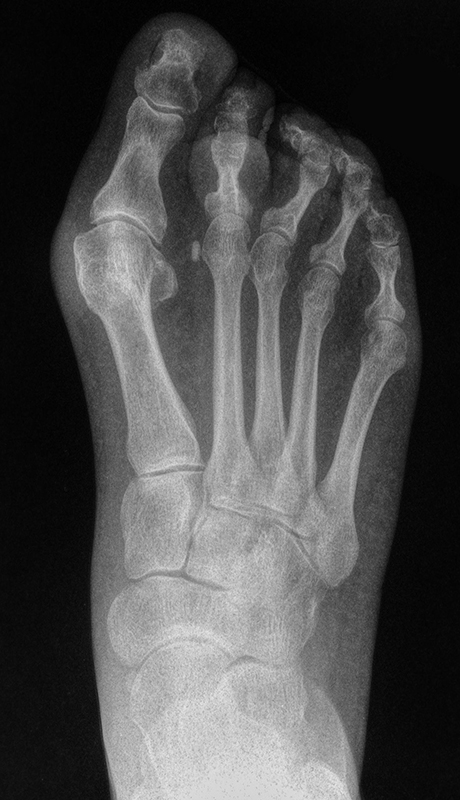

• Röntgenaufnahmen des Fuß in drei Ebenen im Stehen (siehe Abb. 2).

Zum Lesen der Bildbeschreibung und zur Vollansicht bitte das Bild anklicken. Bild: M. Walther.

• Postoperative Röntgenkontrolle in 2 Ebenen vor der Entlassung.

• Nach 6 Wochen erneute Röntgenkontrolle und Wechsel auf einen orthopädischen Maßschuh oder Diabetesschutzschuh, abhängig von Fußdeformität und weiteren Risikofaktoren.